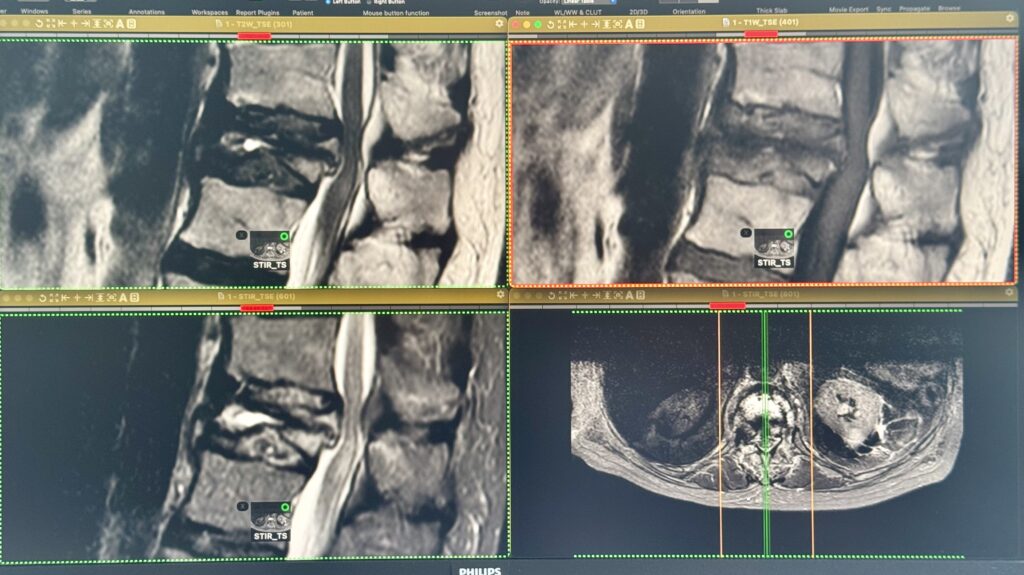

Figura 1: Imagini de Rezonanță Magnetică preprocedural

Examinarea IRM evidențiază: ”tasare cuneiformă cronică, acutizată, a corpului vertebral T12, înălțimea minimă a acestuia fiind de aproximativ 7-8mm în compartimentul mijlociu; se evidențiază traiecte de impactare trabeculară orizontale, unele cu fluid sign inclus, extinse către versantul posterior, cu interesarea pediculului drept; bombare intracanalară de  aproximativ 5mm a zidului posterior, predominant în jumătatea superioară, fără detașare posterioară de fragmente osoase; se asociază modificări edematoase ce interesează corpul vertebral, predominant în jumătatea stânga, ambii pediculi, dar și discurile supra- și subiacent și în țesuturile moi perivertebrale regionale”.